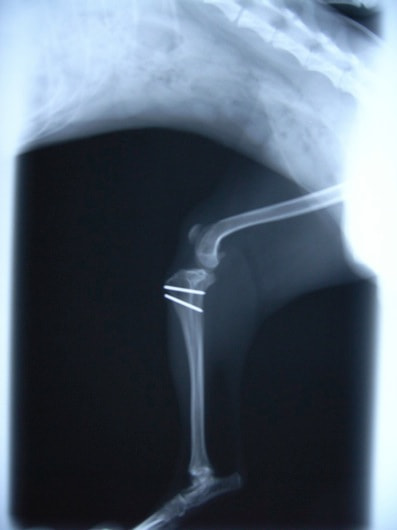

■ 症例20 ポメラニアン 8ヶ月 1.8kg

左右膝蓋骨脱臼 グレードⅢ

2ヶ月前から間欠的跛行が認められ、両膝の膝蓋骨脱臼整復術を行った。

手技は縫工筋及び内側広筋の解放、脛骨粗面の外側転位、滑車ブロック形造溝術、内外側関節包の縫縮を選択し実施した。

右側の膝蓋骨脱臼は上記手技で整復されたものの、左側はそれのみでは膝蓋骨が浮く様子が認められた。その為、PDS縫合糸にて膝蓋靱帯を1糸のみ縫合し、靱帯の縫縮を行った。

膝蓋骨脱臼は膝関節における膝蓋骨の内外側の脱臼と定義されるが、時として単純な内外の脱臼ではなく、膝蓋骨が大きく前方に浮き上がるように脱臼する場合がある。特にトイプードルやポメラニアンといった犬種に多く認められる。

内側脱臼に加えて前方への浮き上がりを矯正する為に、従来より脛骨粗面転移により膝蓋靭帯を外方と下方に引っ張り、固定する方法を選択する。膝蓋骨の前方への浮き上がりが軽度の場合は、従来法ではなく関節包の縫縮で対応していた。しかし、一部の症例で膝蓋骨の動きが悪くなり伸展機構が円滑に機能せずロボット様歩行になるケースがあった。

その為、膝蓋靭帯自体を縫縮する方法を採用した。この方法により、膝関節の伸展機構を妨げず膝蓋骨の軽度の浮きを矯正することが可能となった。

本症例の経過は良好である